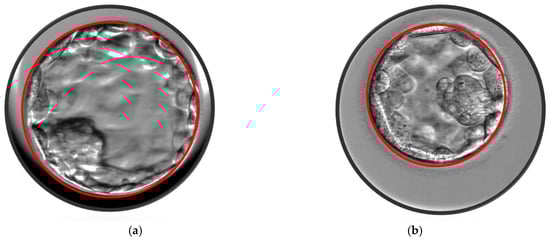

2.3. Blastocyst Morphometric Evaluation